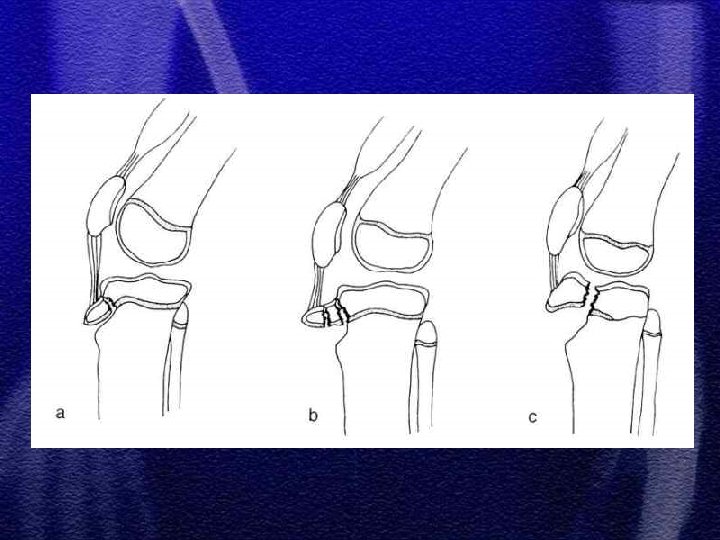

§ W zależności od mechanizmu urazu spotykamy różne typy złuszczeń od I do IV wg Saltera-Harrisa § Złuszczenia typu I i II leczenie zachowawcze gips - 4 tyg. § Złuszczenie typu III i IV leczenie operacyjne - śruby, druty Kirschnera § Złuszczenia wielopłaszczyznowe typ II i III występujące jednocześnie w nasadzie dalszej kości piszczelowej